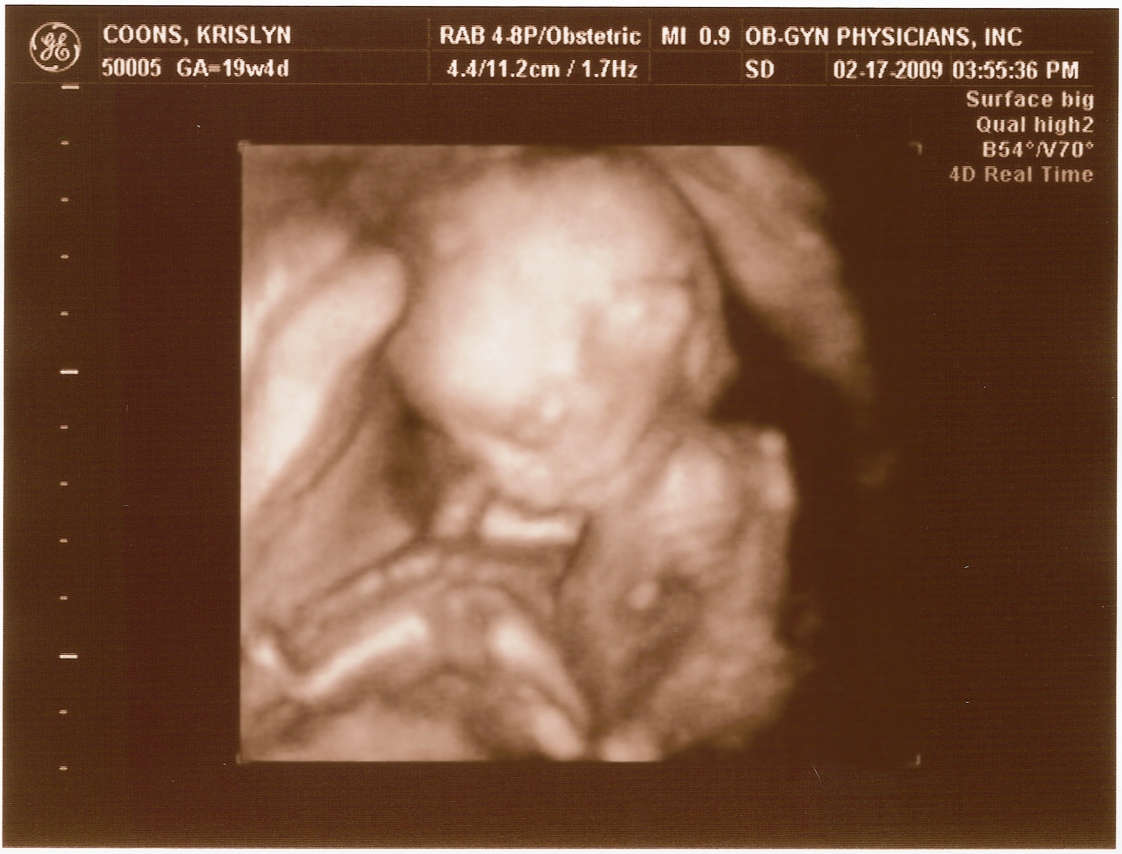

2.17.2009

First ultrasound! The baby measures right on target and appears to be developing normally. All looked and sounded great. Krislyn is finally gaining some baby weight too!

Ultrasound Pictures

20 weeks -